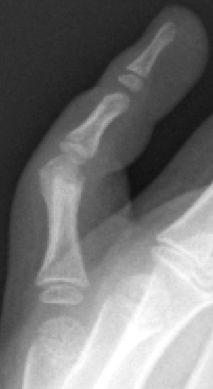

D2. Fracturas diafisarias

Menos frecuentes en la edad pediátrica debido a la estabilización del periostio y la cobertura de partes blandas (tendones flexores). Por lo general, estas fracturas se tratan de manera conservadora permitiendo hasta 30° de angulación en el plano del movimiento, siempre que exista potencial de remodelación (Figura 22). Se debe valorar la inestabilidad del trazo de fractura, la rotación y el acortamiento para indicar una reducción cerrada y estabilización con agujas de Kirschner cruzadas.

Figura 22: a, b- Fractura diafisaria F1 5º dedo mano izquierda con leve desplazamiento y c- evolución posterior.